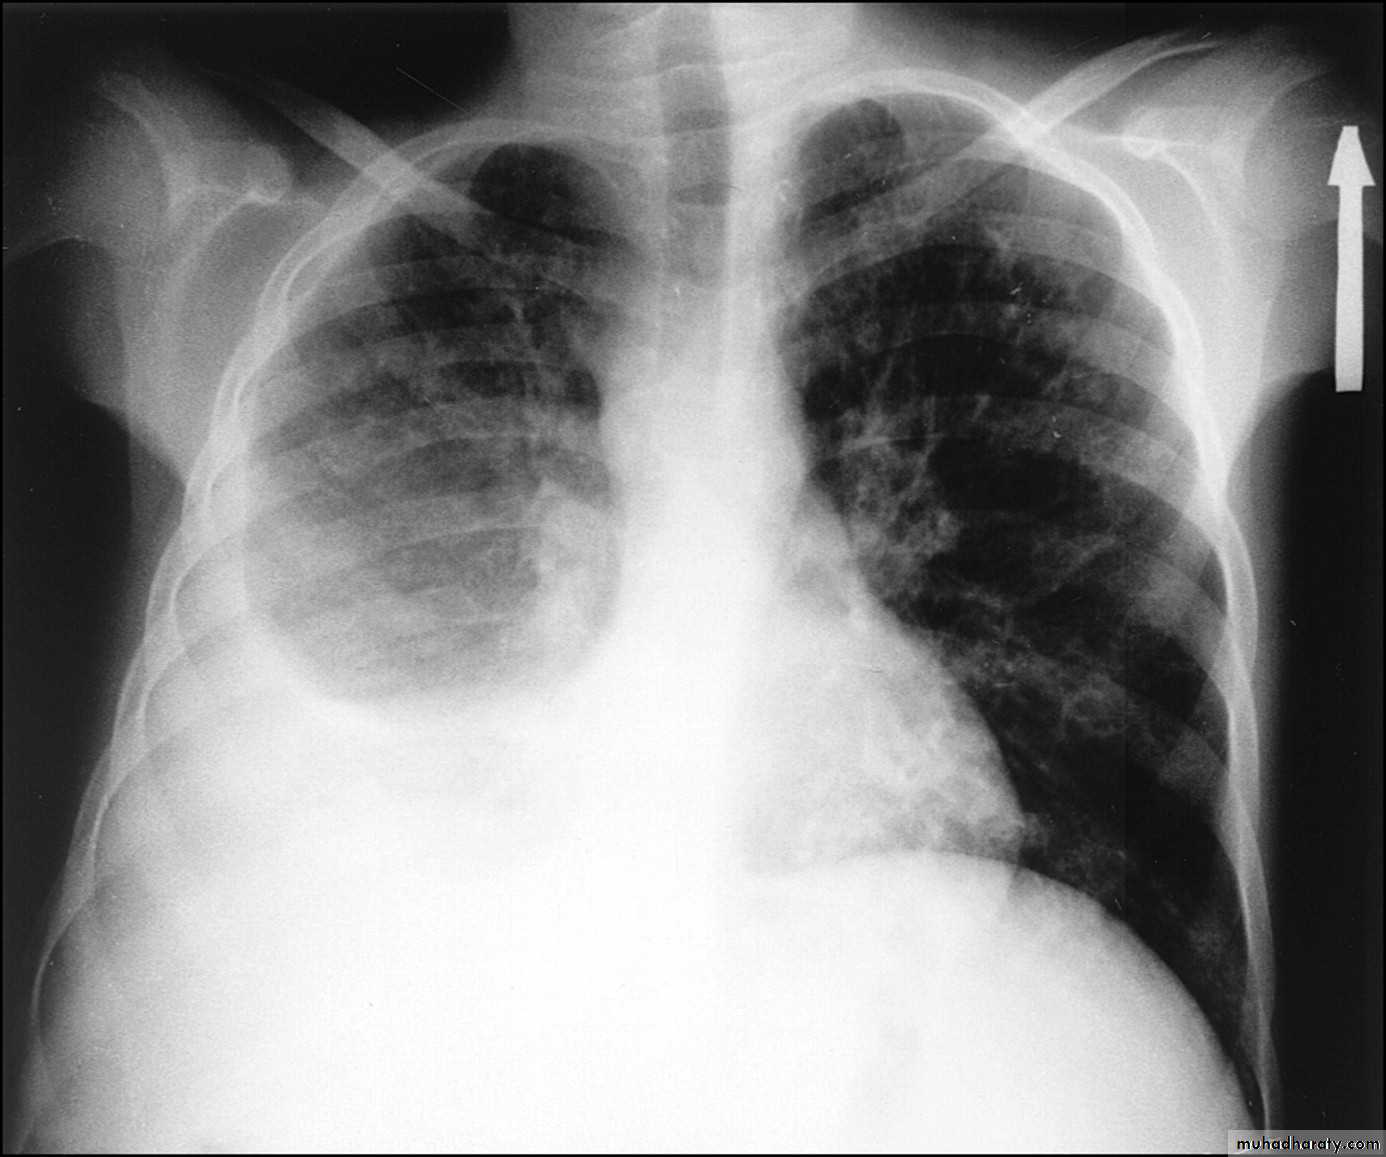

Left upper lobe collapse has distinctive features but can be challenging to identify on chest radiographs by the uninitiated.

Radiographic features

The left upper lobe collapses anteriorly becoming a thin sheet of tissue apposed to the anterior chest wall, and appears as a hazy or veiling opacity extending out from the hilum and fading out inferiorly . It thus reverses the normal slight increase in radiographic density seen as you move down the lung (due to increased thickness of the chest soft tissues).

Parts of the normal cardiomediastinal contour may also be obliterated where the left upper lobe, particularly the lingula abut the left heart border. The anterior parts of the aortic arch are also often obliterated from view.

In some cases the hyperexpanded superior segment of the left lower lobe insinuates itself between the left upper lobe and the superior mediastinum, sharply silhouetting the aortic arch and resulting in a lucency medially. This is known as the luftsichel sign.

The left hilum is also drawn upwards, resulting in an almost horizontal course of the left main bronchus and vertical course of the left lower lobe bronchus.

Non-specific signs indicating left sided atelectasis will also be present, including:

elevation of the hemidiaphragm

'peaked' or 'tented' hemidiaphragm: juxtaphrenic peak sign

crowding of the left sided ribs

shift of the mediastinum to the left

On lateral projections the left lower lobe is hyperexpanded and the oblique fissure displaced anteriorly. There is associated increase in the retrosternal opacity.